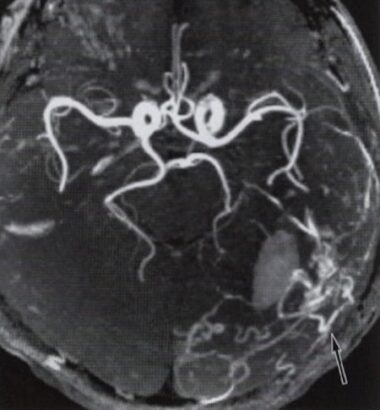

頭部MRIで発見し、脳血管造影検査で確定診断と重症度を判定します。

当然いきなり、入院して脳血管造影検査をする患者さんはいませんので、頭部MRIでの検査が重要になります。専門的な話ですが、Time of flightによるMRA検査を行い、MIP画像までしっかりと診ないと見過ごしてしまうことがあります。この病気の診断には専門性と経験が必要なため、脳神経外科専門医や放射線科専門医の読影が必須となります。

MRA検査

MRI検査の中のMRA(Magnetic Resonance Angiography:磁気共鳴血管撮影法)で、診断が可能です。しかし、診断は専門的な知識と経験が不可欠です。脳神経外科専門医によるMRI検査が必須と考えております。